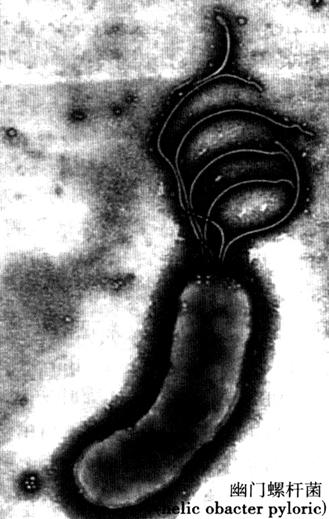

值得一提的是,自Barry J.Marshall(巴里·马歇尔)和J.Robin Warren(罗宾沃伦)1983在Lacent(《柳叶刀》)(1983.1(8336):1273)上发表第一篇关于幽门螺杆菌(Helicobacter pyloric,Hp)的论文以来(图9-16),引起了全球学者对Hp这个小细菌的莫大关注,相关的文章也络绎不绝地涌现,对以往不少学者提出“一旦溃疡,终身溃疡”的悲观论点进行了大胆的质疑,无疑是临床消化病学实践领域的一个重要里程碑,从而彻底改变了以往100多年来“没有酸,就没有溃疡”的传统观念。研究证实90%十二指肠溃疡和80%胃溃疡都是由Hp所引起的。研究发现“定居”在胃内的Hp可产生毒素和有毒性作用的酶,而损害了胃黏膜,破坏了正常的胃黏膜屏障,使机体产生炎症和免疫反应,导致胃泌素的分泌减少,最终使胃部疾病的发生。所以,在根除Hp后胃溃疡病真的消失了,有80%的溃疡病可以被永久性治愈;经过长期随访观察,溃疡病复发率可降至10%以下。深入的实验研究显示,Hp与胃癌的发生关系也十分密切。此乃由于Hp可引起细胞过度增殖,使DNA易受到损伤,它还可引起原癌基因激活,抑癌基因失活,以致癌基因过度表达及基因突变等。因此,被认为Hp是胃癌的一个启动因子。

图9-16 幽门螺杆菌

然而,Hp究竟如何能在胃酸度很高(空腹时胃液pH值为0.9~1.5,有食物时为2~3)的环境在胃内存活下来呢?在显微镜下Hp呈螺旋状结构,其一端有4~6根鞭毛;螺旋状的结构为Hp在黏液中运动提供良好的基础,它的鞭毛摆动为Hp运动提供了足够的动力,使Hp能迅速穿过胃的黏液层,并覆盖在胃黏膜上。同时Hp能产生一种尿素酶和一些蛋白质,如热休克蛋白,一方面增强了Hp对酸的抵抗力,同时还会产生一种抑制胃酸分泌的蛋白,使局部的胃酸分泌减少,有利于Hp的“寄居”。研究还发现Hp能产生过氧化物歧化酶和触酶,借此可躲避中性白细胞对Hp的“追杀”;这样Hp就可以附着胃、十二指肠而避免与食物一起被排送到肠道里去,从而得以永久定居在胃内,成为溃疡病的“元凶”。